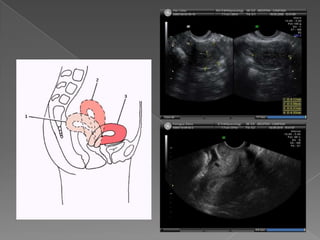

 Durante elestudio ecográfico el útero es una referencia fiable.  Localización central  Tamaño relativa/ grande  Típica forma de pera  Normal : leve desvío de línea media  Desvío marcado: masas / adherencias

 Relación ejeuterino/ vagina  Anteversión o Retroversión  Relación cérvix / cuerpo  Anteverso flexión o retroversoflexión

Importante en procedimientos:  Histeroscopía  Colocación de DIU  Legrado  Transferencia embrionaria  Tener en cuenta : posición según lleno vesical